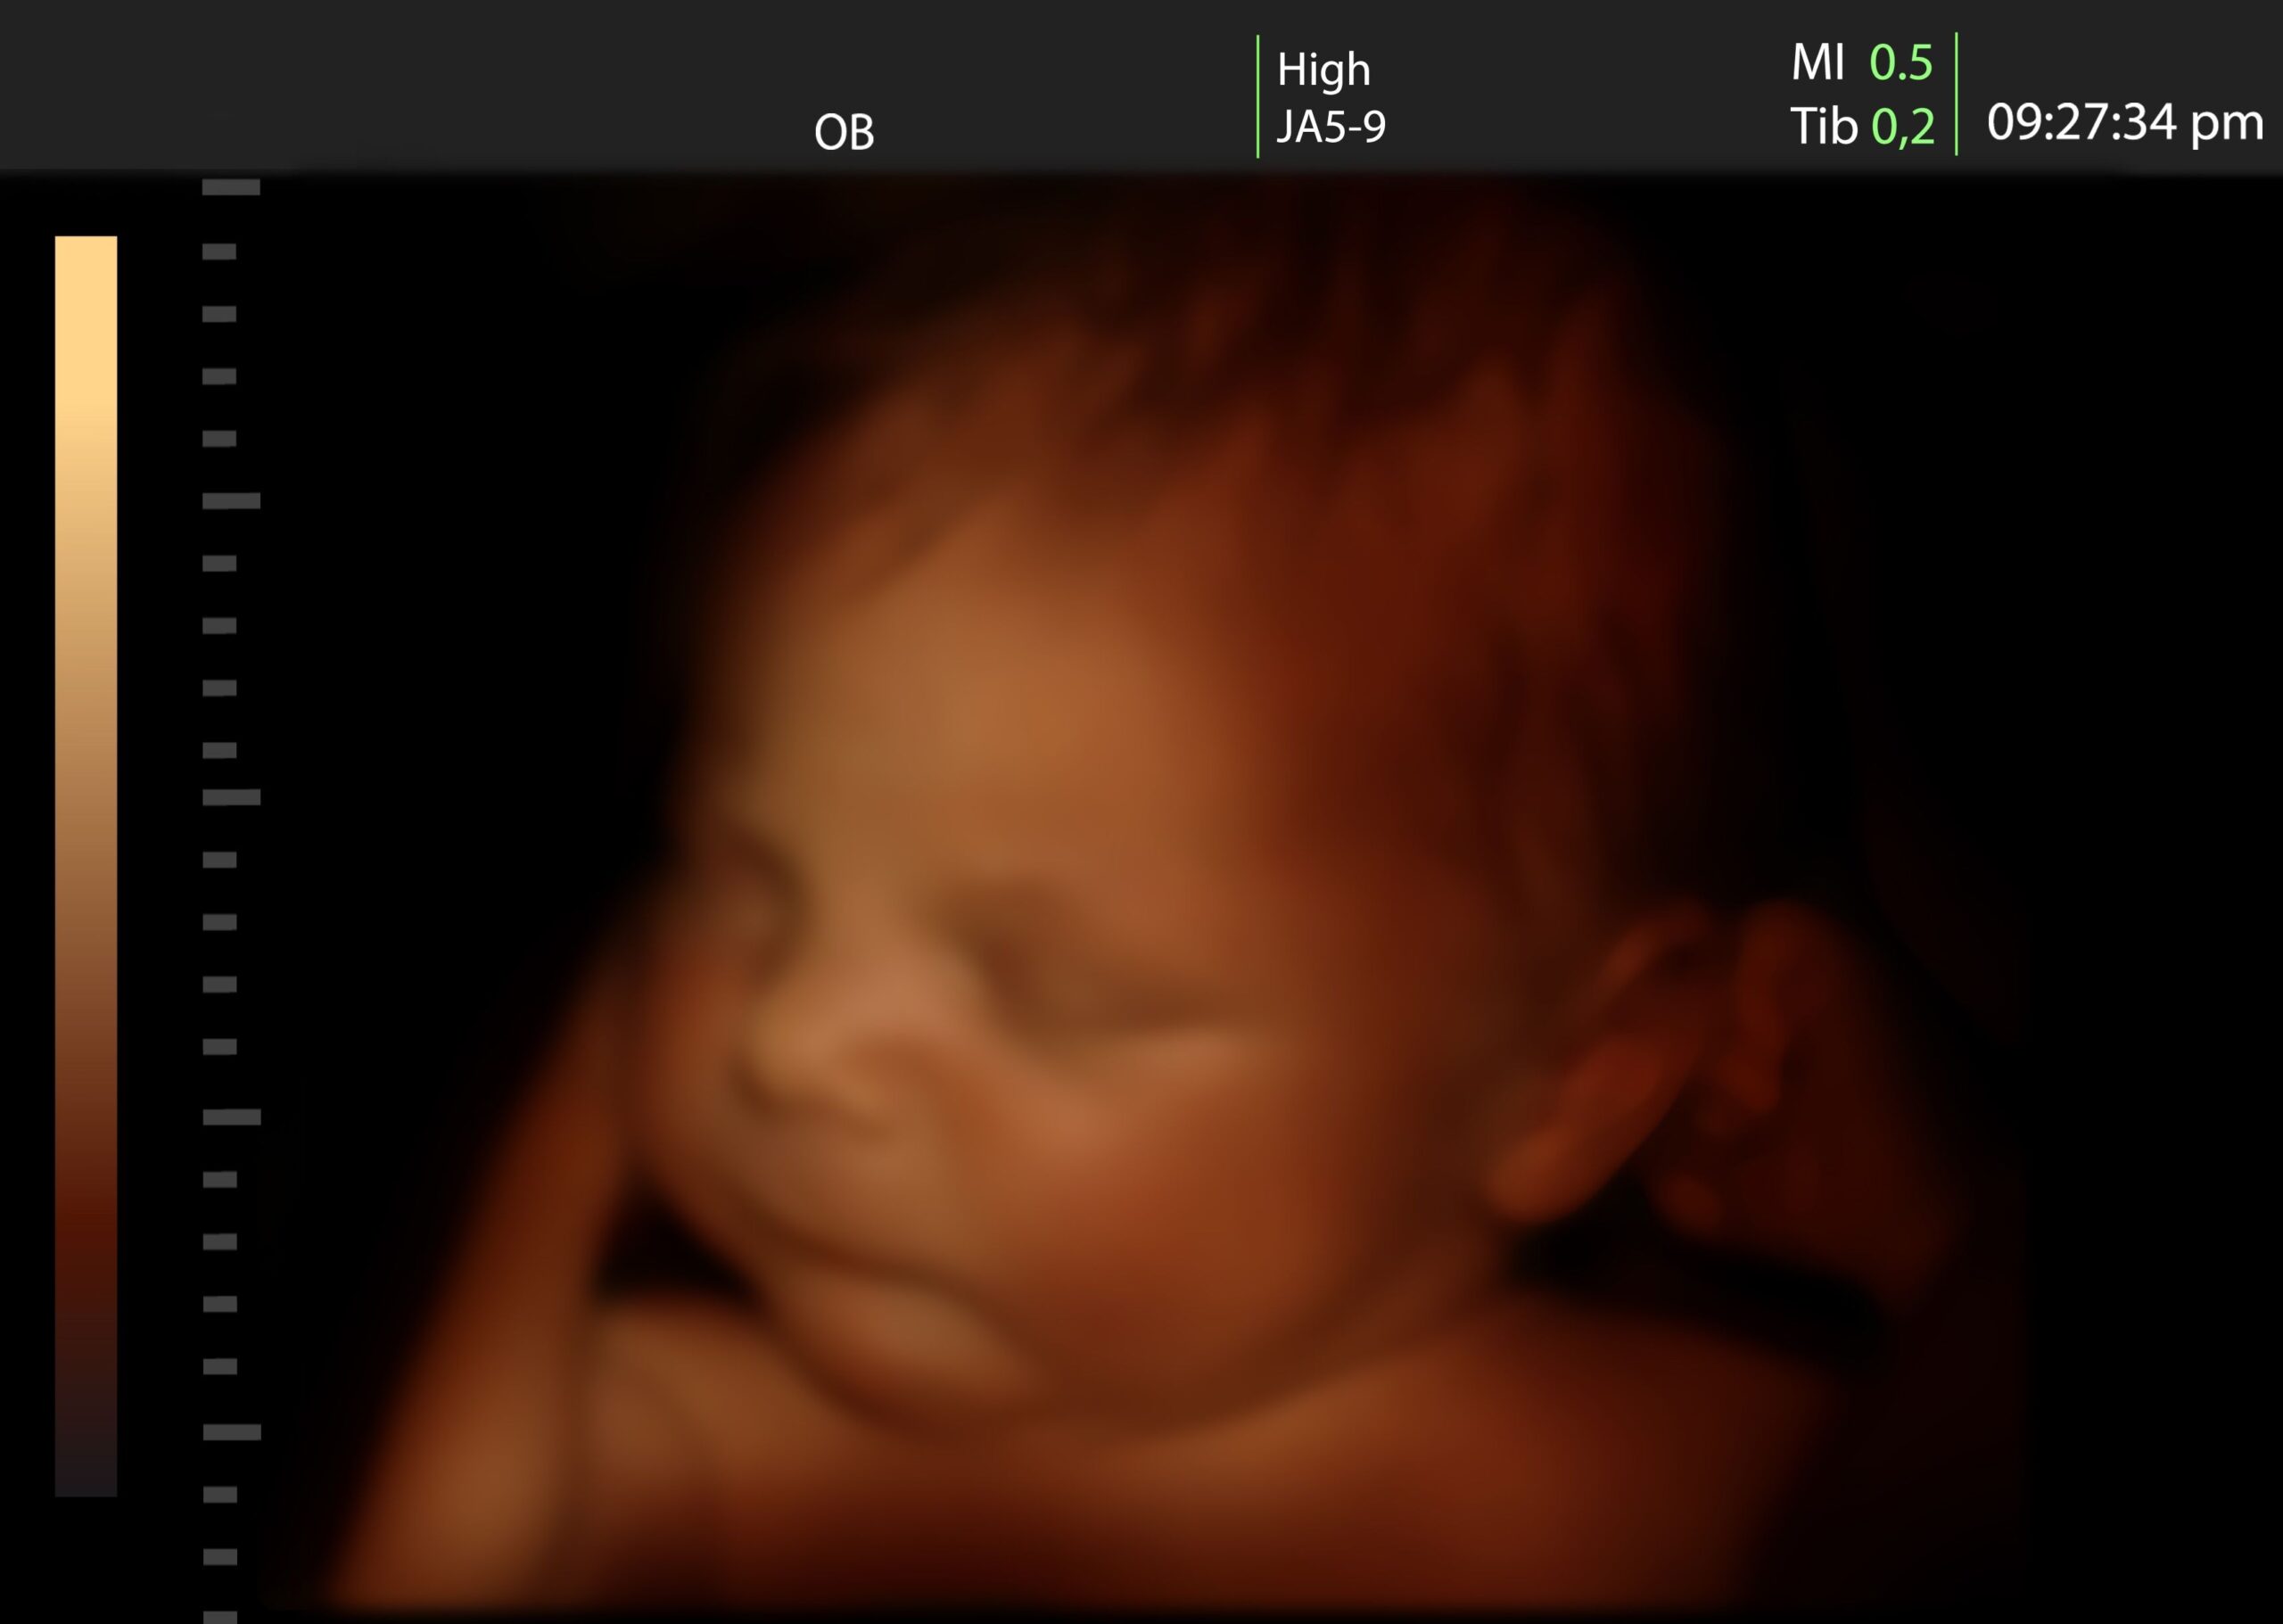

Rengeteg kutatás foglalkozott már a magzati kommunikációval, észleléssel. Az elmúlt évtizedekben bebizonyosodott, hogy a magzat képes a környezetéből származó ingerek fogadására, feldolgozza a különböző információkat, és válaszolni is képes. A magzat testmozgásokkal, szem- és szájmozgásokkal reagál, valamint a szívritmusa is váltakozó lehet az egyes ingerek hatására.

A babád már a 6. héten mozgolódik, persze te ebből még semmit sem érzel. Ezek a mozgások még többnyire spontán testmozgások. A 8-9. héten különböző intenzitású, azaz lassú és gyors mozgások is megfigyelhetők, ám ebből az anya még mindig nem érez semmit. A 10. héten már a végtagjait mozgatja, légzőmozgásokat végez, kialakulnak a szopó- és nyelőmozgások is. A második trimeszterben, úgy a 16. hét környékén kialakulnak a lassú szemmozgások, a 23. hétre pedig a gyorsak is.

A magzat már a 14. héttől fogva teljesen úgy mozog, mint egy újszülött. A magzatmozgások, a méhen belül kifejlődő készségek előkészítik a terepet a születés utáni fejlődésnek. E mellett pedig nagy szerepük van a későbbi szülő-baba kapcsolatban is.